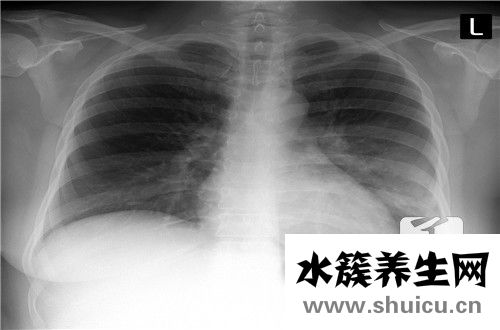

當你的胸部疼痛時,你可能患有心臟病或冠心病,或者你可能由于過度運動而拉傷了肌肉,或者你可能由于胃病而出現胃食管反流。你可以去醫院檢查,消除胃病的可能性,然后進行對癥治療。建議多吃蔬菜和水果,多...